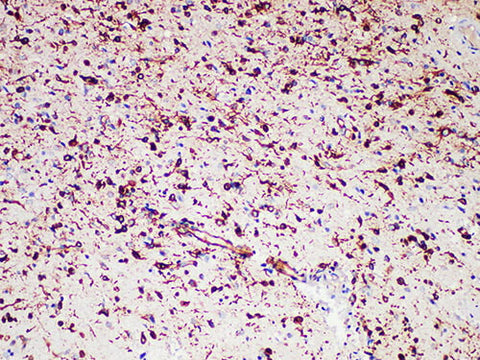

Applications IHC-P

Tissue Specificity Glioma

Nestin is a 200kDa class Ⅵ intermediate filament protein that is mainly expressed in early embryonic neuroepithelial stem cells and during tendon and neuromuscular joint development. "Nestin is not specific for the central nervous system because it identifies not only the most primitive neuroepithelium but also other embryonic tissues." Nestin is expressed in almost all glioblastomas and melanomas (primary and metastatic), but it is not expressed in any metastatic carcinoma.